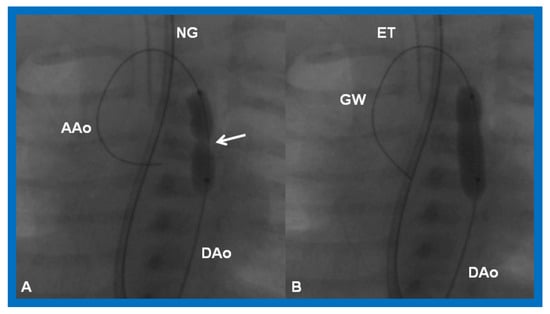

Aortic coarctation may develop or a missed neonatal diagnosis may manifest subsequent to Stage I palliation, or aortic recoarctation may occur following prior surgery. These may be detected by physical examination (decreased and/or delayed femoral arterial pulses and higher systolic blood pressure in the arm than leg) or imaging studies such as echocardiogram or MRI/CT. The indications for intervention are CHF or hypertension along with a peak systolic gradient higher than 20 mmHg. At this stage, balloon angioplasty [69,70,72,90] (Figure 21) may be carried out.

Cineradiographic frames in 20° left anterior oblique view demonstrating a balloon angioplasty catheter placed across the aortic coarctation. Note waisting (arrow) of the balloon (A) during the initial phases of balloon inflation, which was abolished (B) on further inflation of the balloon. AAo, ascending aorta; DAo, descending aorta; ET, endotracheal tube; GW, guide wire; NG, nasogastric tube. Modified from Reference [90].